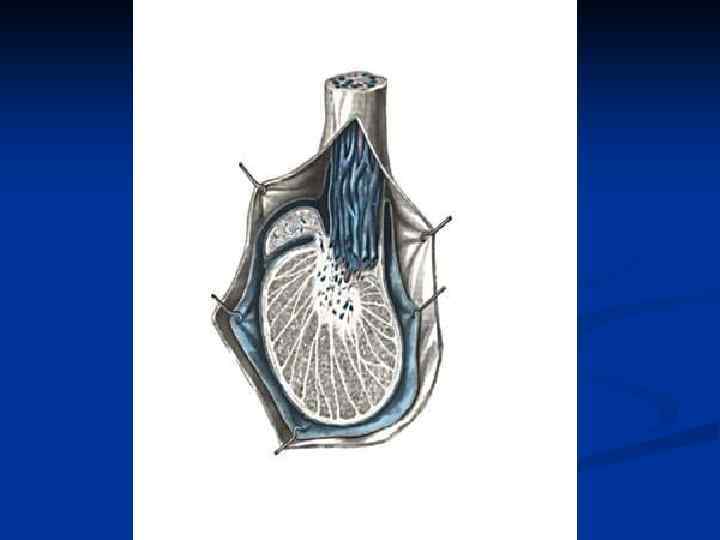

Семенной канатик, funiculus spermaticus – круглый тяж (15 -20 см) от глубокого пахового кольца до верхнего конца яичка, образующийся в процессе опускания яичка. Состав: 1. Семявыносящий проток 2. Яичковая артерия 3. Артерия семявыносящего протока 4. Лозовидное венозное сплетение 5. Лимфатические сосуды яичка и придатка 6. Нервы 7. Влагалищный отросток Оболочки, tunicae funiculi spermatici (изнутри наружу): 1. Внутренняя семенная фасция 2. Мышца поднимающая яичко 3. Фасция мышцы поднимающей яичко 4. Наружная семенная фасция

Семенной канатик, funiculus spermaticus – круглый тяж (15 -20 см) от глубокого пахового кольца до верхнего конца яичка, образующийся в процессе опускания яичка. Состав: 1. Семявыносящий проток 2. Яичковая артерия 3. Артерия семявыносящего протока 4. Лозовидное венозное сплетение 5. Лимфатические сосуды яичка и придатка 6. Нервы 7. Влагалищный отросток Оболочки, tunicae funiculi spermatici (изнутри наружу): 1. Внутренняя семенная фасция 2. Мышца поднимающая яичко 3. Фасция мышцы поднимающей яичко 4. Наружная семенная фасция